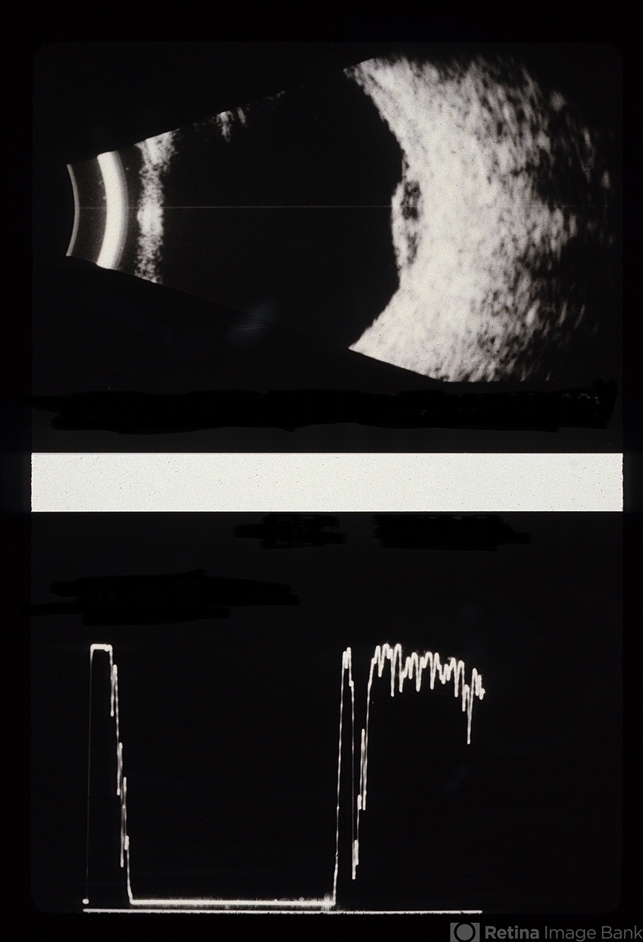

75-year-old female, amelanotic malignant melanoma.